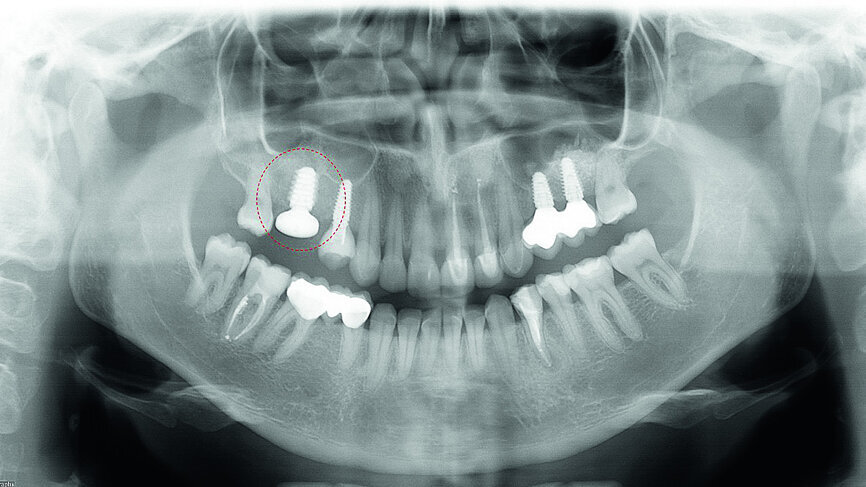

In November 2017, a 39-year-old female patient came to an initial appointment at White Clinic owing to tooth pain (tooth #16). A clinical and radiographic examination were performed, including a periapical radiograph, CBCT scan (Carestream 9500, Carestream Dental), and intra- and extraoral photographs (Figs. 1–3).

In the clinical and radiographic evaluation, it was observed that tooth #16 presented an invasive cervical resorption at the mesiobuccal root. The treatment plan established was dental extraction with immediate implant placement. The tooth had been previously re-treated endodontically and restored with a definitive ceramic crown. Due to the current situation of the tooth, although the protocol in White Clinic is to preserve teeth, it had indication for immediate extraction. Also due to the lack of time, our digital team was not able to produce a surgical guide for the implant placement. Therefore, the treatment plan included a surgical phase and a digital prosthetic phase.